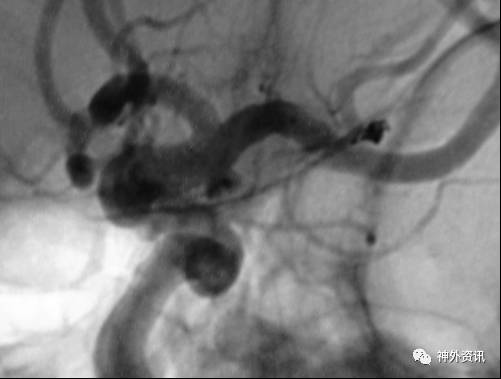

猪尾塑形

猪尾左行和右行

微导管尾端向下直立,头端向前弯曲时,头端相对左偏为左行,右偏为右行。

指向下方的颈内动脉眼段或床突段动脉瘤(颈动脉窝动脉瘤)

指向下方的颈内动脉后交通段或脉络膜段动脉瘤

(1)左侧颈内动脉-猪尾左行

(2)右侧颈内动脉-猪尾右行

病例一

病例二

病例三

病例四